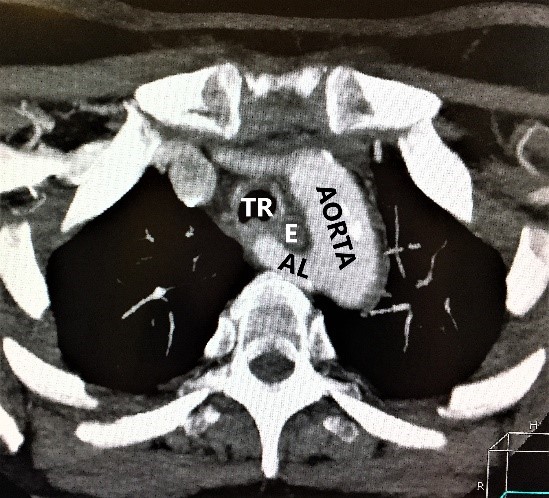

- На уровне правого грудино-ключичного сочленения AL и правая общая сонная артерия располагаются отдаленно друг от друга. Данная сонографическая картина выявлена у всех 4 пациенток (рис. 3).

- На уровне правого грудино-ключичного сочленения AL и правая общая сонная артерия располагаются перпендикулярно друг к другу. Данный признак выявлен у всех пациенток (рис. 4).

Рис. 3. Пациентка 58 лет, ИМТ – 21,7. а – цветное дуплексное сканирование сосудистого пучка правой половины шеи линейным датчиком на уровне правого грудино-ключичного сочленения. Правая общая сонная артерия прослежена до места “пересечения” с трахеей (БЦС не выявлен). AL располагается на значительном расстоянии от правой общей сонной артерии. б – интраоперационная картина. НВГН I типа (по Avisse–Toniato) имеет нисходящее направление и состоит из двух веток (стрелки). в – аксиальный КТ-скан с ангиографией сосудов дуги аорты. AL располагается позади трахеи и пищевода. г – компьютерная трехмерная реконструкция демонстрирует синтопию AL с общей сонной артерией. AL является последней, четвертой ветвью дуги аорты. ACC – arteria carotis communis dexter, TR – trachea, E – esophagus. VJI – vena jugularis interna dexter, NV – nervus vagus dexter.

Рис. 4. Пациентка 68 лет, ИМТ – 31,6. а – УЗИ сосудистого пучка правой половины шеи линейным датчиком в В-режиме. б – цветное дуплексное сканирование сосудистого пучка правой половины шеи линейным датчиком. AL расположена параллельно плоскости сканирования. Правая общая сонная артерия и трахея находятся перпендикулярно относительно датчика. в – интраоперационная картина. Мобилизована правая доля ЩЖ, отведена медиально. НВГН состоит из двух веток (стрелки). г – интраоперационная картина. Выполнена тиреоидэктомия. НВГН IIA типа (по Avisse–Toniato) имеет горизонтальный ход. д – аксиальный КТ-скан с ангиографией сосудов дуги аорты. AL располагается позади трахеи и пищевода. е – компьютерная трехмерная реконструкция демонстрирует синтопию AL с общей сонной артерией. AL является последней, четвертой ветвью дуги аорты. ACC – arteria carotis communis dexter, TR – trachea, E – esophagus.